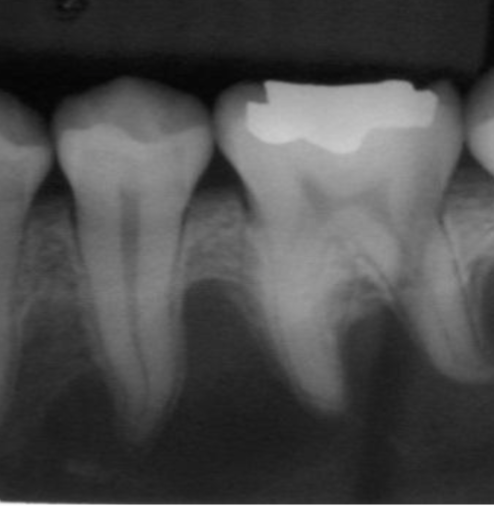

root resorption

shortened/ irregularly shaped root apex

scalloping

radiolucent lesion that extends between the roots, seen in traumatic bone cyst (TBC)